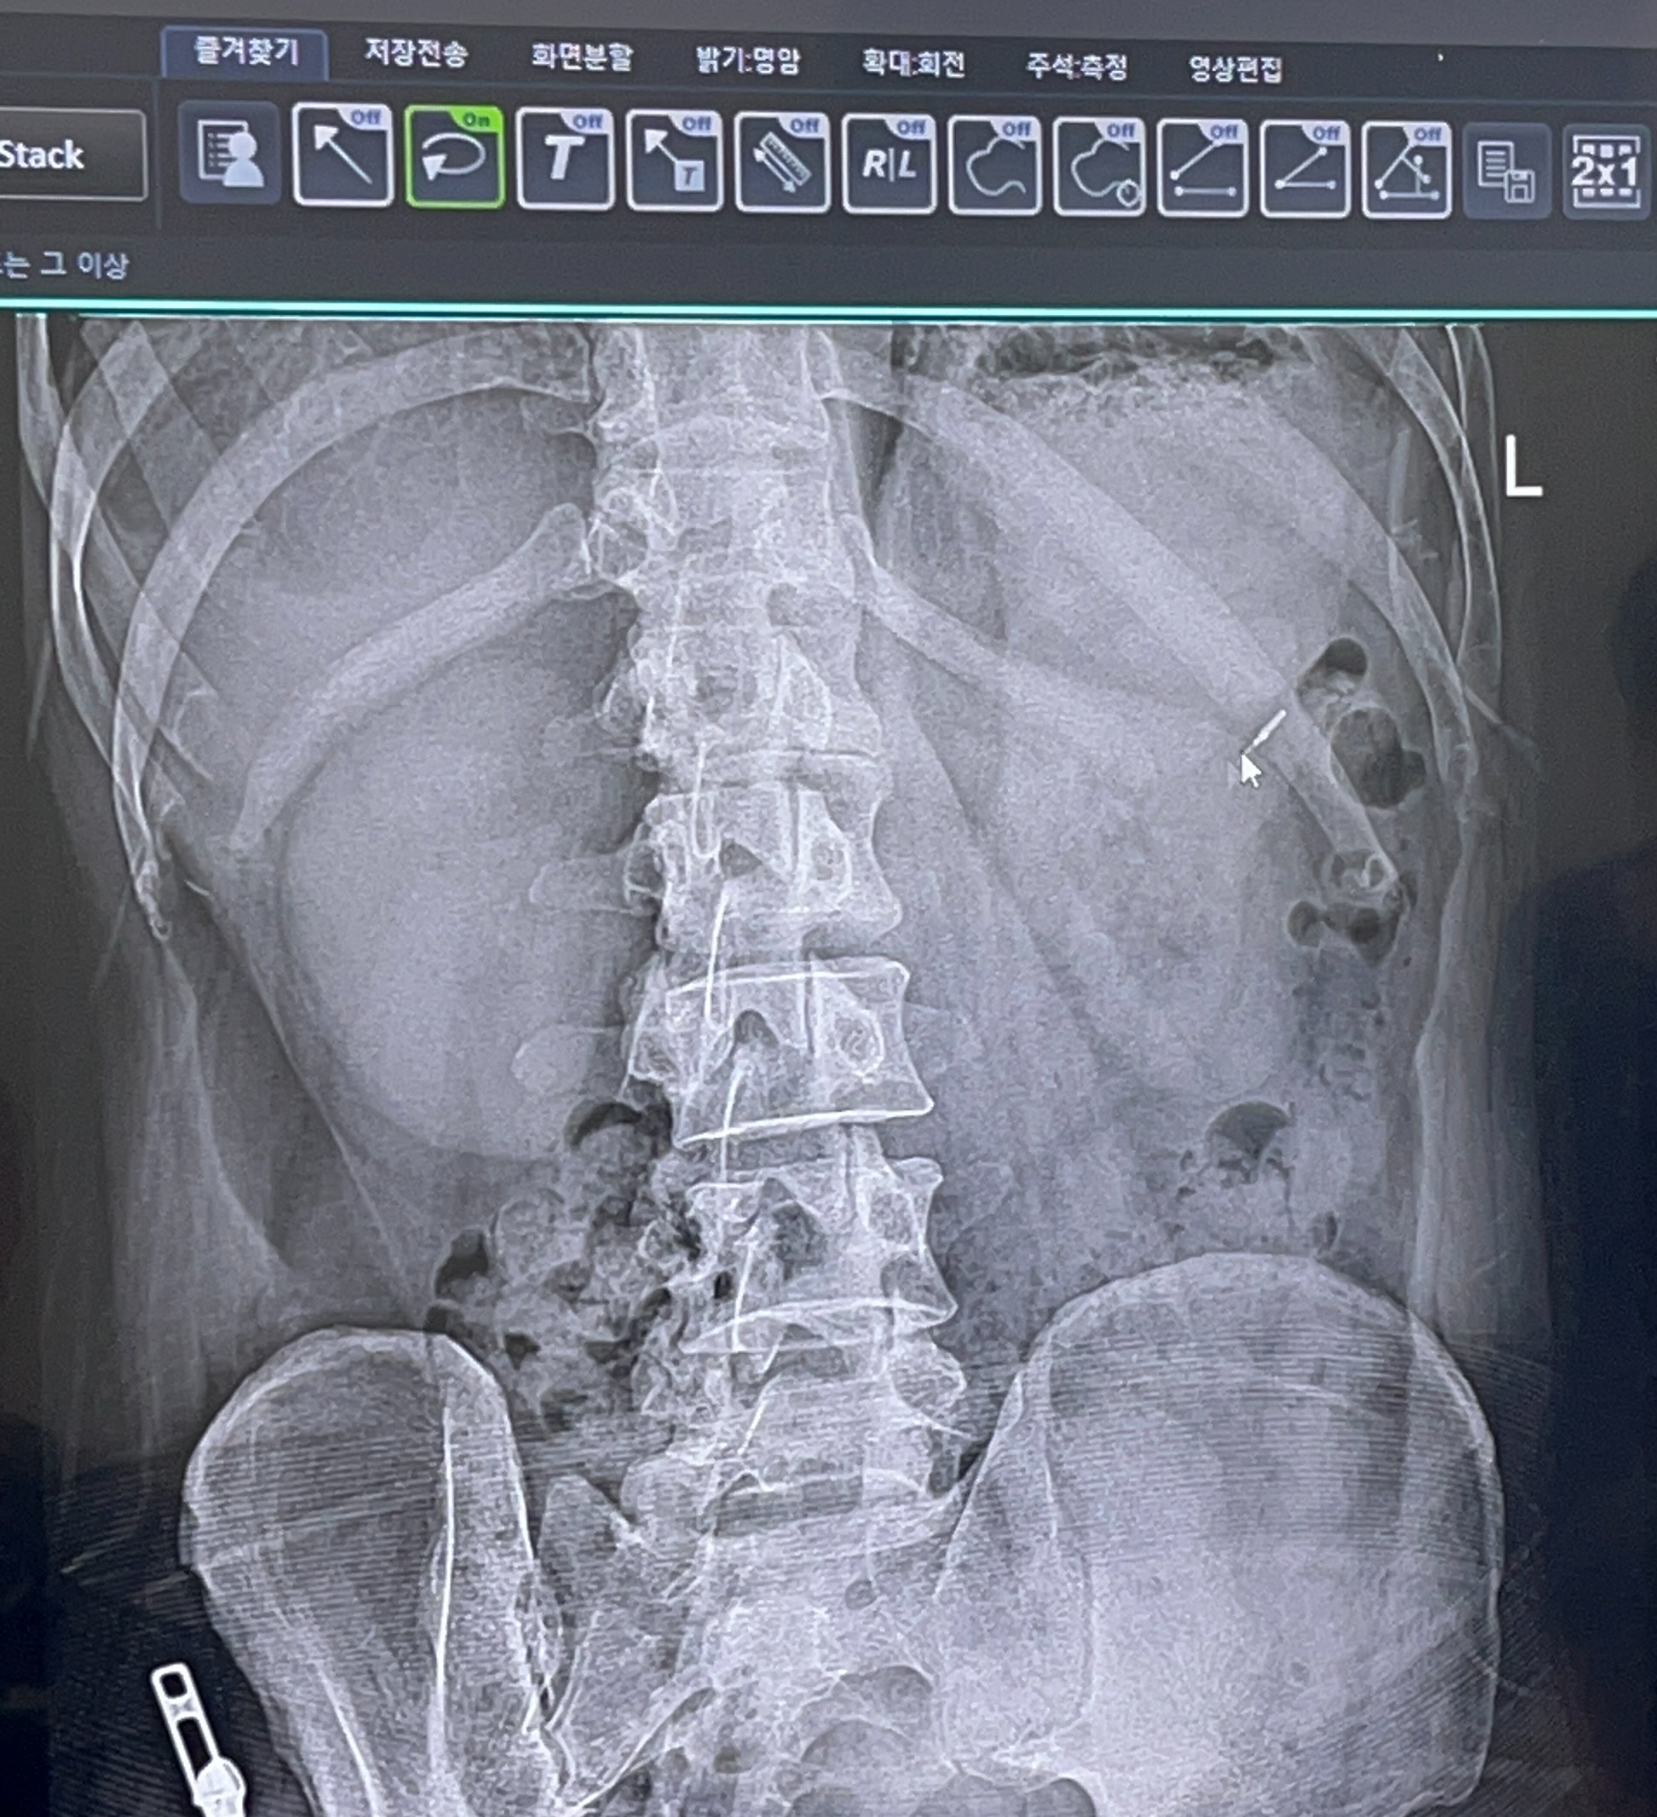

우연치않게 허리 사진을 찍어보다가 발견된 이상한 물질

폐 앞쪽으로 가슴쪽에 이상한? 물질이 찍혀있음.

옆으로 돌린 사진에도 나와 있음

넌 도대체 뭐니?

아마도 내시경 할때에 용종 같은거 떼고나면 붙여놓는 클립처럼 보인다고.

22년도에 찍은 엑스레이 사진에도 떡하니 있다.

그것도 한개가 아닌 두개!!!!